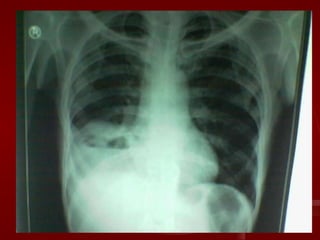

On the basis of above history, examination and investigations the presumptive diagnosis is------ Right middle and lower lobe consolidation with cavitation

On the basisof above history, examination and investigations the presumptive diagnosis is------ Right middle and lower lobe consolidation with cavitation